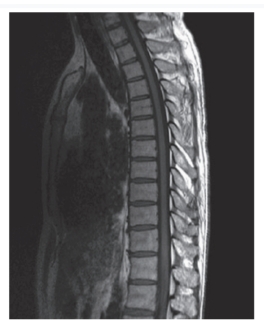

-Refer to the figure. What radiographic view is this?

A) AP

B) Lateral

C) Oblique

D) Coronal

Lateral

3

-Refer to the figure. The appearance of the osseous deformity infers what mechanism of injury?

A) Extension

B) Hyperextension

C) Flexion

D) Side-bending

Flexion

4

-The eighth and ninth vertebral deformity is associated with osteoporosis and the most likely diagnosis is:

A) Vertebral compression fractures

B) Tuberculosis of the spine

C) Herniated nucleus pulposus

D) Osteomyelitis of the spine